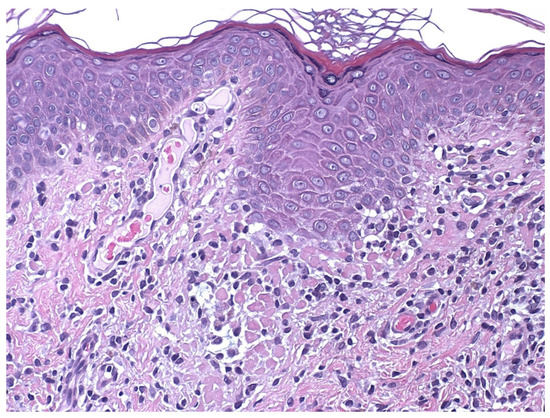

4. Histopathology